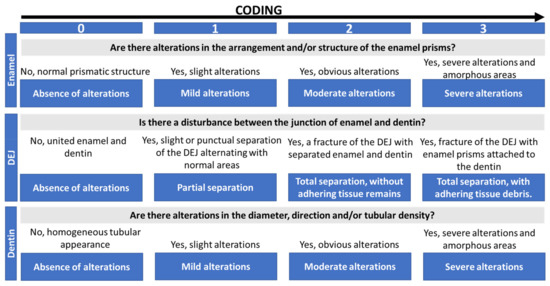

The morphological changes were classified into 4 categories (Scheme 1) in order to be able to carry out correlations between the types of OI studied. The classification was created with the aim of standardizing the depth of observation in the samples. The presence of clinical or radiographic dental alterations and changes in tooth colour were recorded dichotomously. The severity of the clinical–radiographic alteration was recorded by the simultaneous presence of clinical–radiographic changes (severe), exclusively radiographic alteration (moderate) or the absence of clinical–radiographic pathology (mild).

Scheme 1.

Coding of ultrastructural morphological changes.